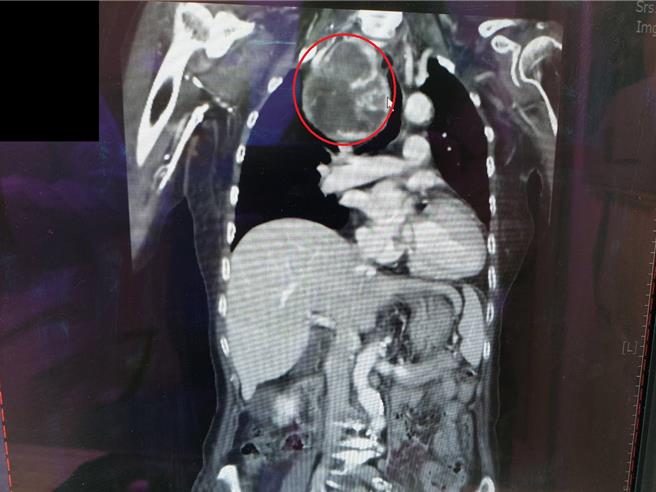

74歲的黃奶奶因在家中突然呼吸急促、感覺吸不到空氣,經就醫急診,由醫師安排胸部X光及電腦斷層檢查後,發現一個將近15公分的巨大甲狀腺腫瘤,直接壓迫氣管,造成呼吸道阻塞。所幸,立即安排緊急手術切除腫瘤,術後三天順利拔除呼吸管,恢復狀況良好。

黃奶奶經檢查發現一顆巨大甲狀腺腫瘤,直接壓迫氣管,造成呼吸困難。(大千醫院提供/謝明俊苗栗傳真)